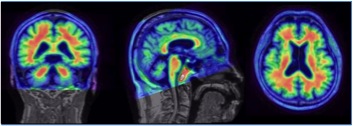

Dr Landau's research focuses on brain changes that occur in healthy aging and Alzheimer’s disease. She uses a variety of neuroimaging techniques, other biomarkers, and health information to understand the neurophysiological processes underlying cognitive decline in Alzheimer's disease and related dementias. Her research has a particular emphasis on the roles of amyloid and tau, measured with positron emission tomography (PET), and neurodegeneration, measured with magnetic resonance imaging (MRI).